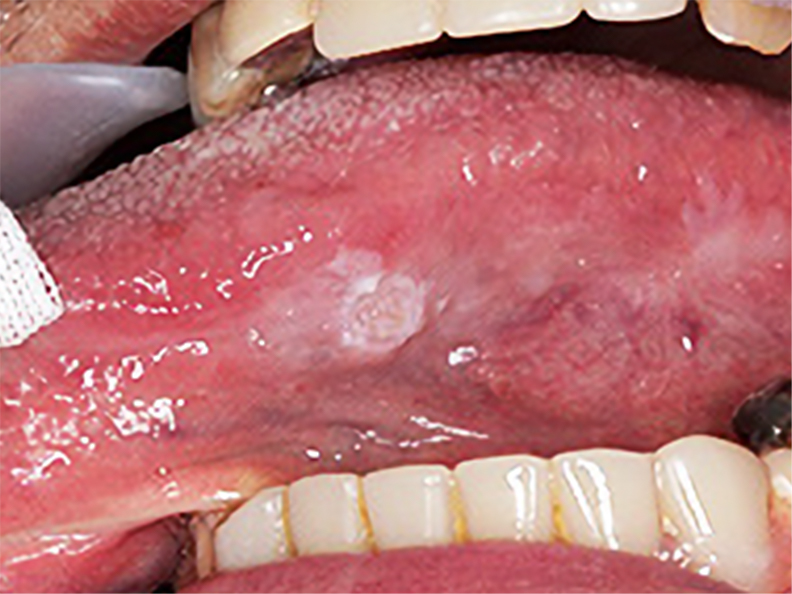

구강암의 초기 증상은 다음과 같습니다:

- 입안의 궤양이나 상처가 3주 이상 지속됨

- 입안에 하얀색 또는 붉은색 병변이 나타남